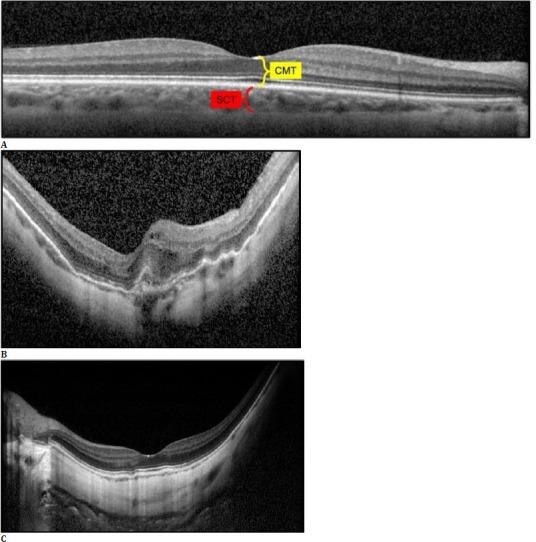

A total of 122 eyes from 78 patients were included. Seventy-five eyes with an AL ranging between 26.00 and 27.49 mm comprised Group 1, and 47 with an AL of ≥ 27.50 mm comprised Group 2. Spectral-domain OCT was performed to measure the central macular thickness, subfoveal choroidal thickness (SCT) and swept-source OCTA was utilized to obtain the data on foveal avascular zone (FAZ) and vascular density (VD) values at the superficial and deep capillary plexuses (SCP and DCP), outer retina (OuR), and choriocapillaris (CC) segments.

材料与方法

纳入78例患者的122只眼。75只AL在26.00至27.49mm之间的眼组成第1组,47只AL≥27.50mm的眼组成第2组。采用光谱域光学相干断层扫描测量中心黄斑厚度、黄斑下脉络膜厚度(SCT),并利用扫频源OCTA获取黄斑无血管区(FAZ)以及浅表和深部毛细血管丛(SCP和DCP)、外层视网膜(OuR)和脉络膜毛细血管(CC)段的血管密度(VD)值数据。